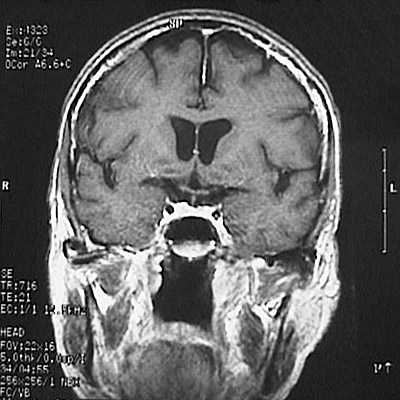

This is a normal coronal T1 weighted enhanced MRI scan demonstrating the frontal lobe and temporal lobe and caudate and putamen and internal carotid artery and insular cortex and lateral ventricle and superior sagittal sinus and corpus callosum.